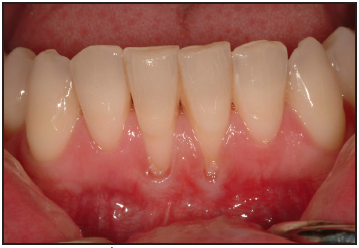

Gingival recession is defined as the reduction of the height of the marginal gingiva to a location apical to the cementoenamel junction, resulting in root surface exposure (Figure 11). Gingival recession can be precipitated by many factors including increasing age, gender, and anatomical factors. Toothbrushing technique, frequency, duration, force of brushing, and the hardness of toothbrush filaments may also contribute to gingival recession.36

Figure 11 – Gingival Recession

Figure 11